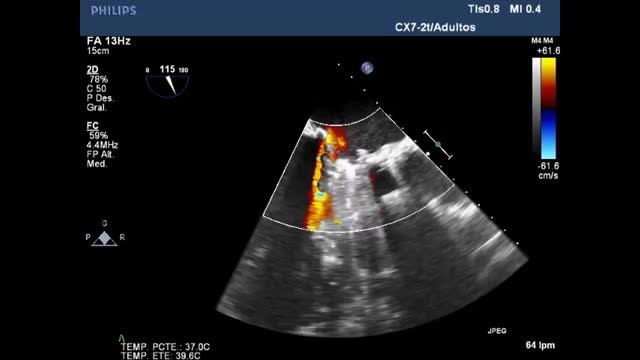

Disfunción protésica (Video 3 en material suplementario)En una primera aproximación mediante la ETT tenemos que prestar especial atención al aspecto, a la apertura y al cierre de las valvas u oclusores, a la presencia de calcificaciones en las valvas o a una densidad ecográfica anómala adherida al anillo de sutura, el oclusor, las valvas, los stents o la caja; y el movimiento de balanceo anormal durante el ciclo cardíaco, siendo necesario completarlo con ETE para una adecuada evaluación.

La aparición de fuga paravalvular siempre constituye un fenómeno patológico29,30, siendo más frecuente en reintervenciones valvulares, pacientes añosos, desbridamiento de calcio del anillo y reconstrucciones aórticas o mitrales. La proporción de circunferencia del anillo afectada determina la gravedad de la fuga paravalvular y puede ser un signo de endocarditis en una etapa más tardía.

Todas las válvulas protésicas generan un cierto grado de obstrucción comparadas con las nativas, dependiendo del diseño, del tamaño y de la posición anular (intra/supra) de las misma, asemejando una estenosis. Es recomendable consultar los gradientes esperados para el diámetro y modelo de prótesis (Apéndices 1 y 2)31-35. Por ello, puede ser difícil diferenciar la obstrucción hemodinámica de una disfunción leve patológica y del desacoplamiento prótesis-paciente (DPP) o mismatch (tabla 3, fig. 4, Video 4 en material suplementario)36.

En posición aórtica, la morfología triangular del contorno de la velocidad Doppler, con un tiempo de aceleración corto, nos informa de normofunción. Conforme avanza la obstrucción, la morfología de la velocidad Doppler se volverá más redonda, alcanzando el flujo máximo más tardío (fig. 4).